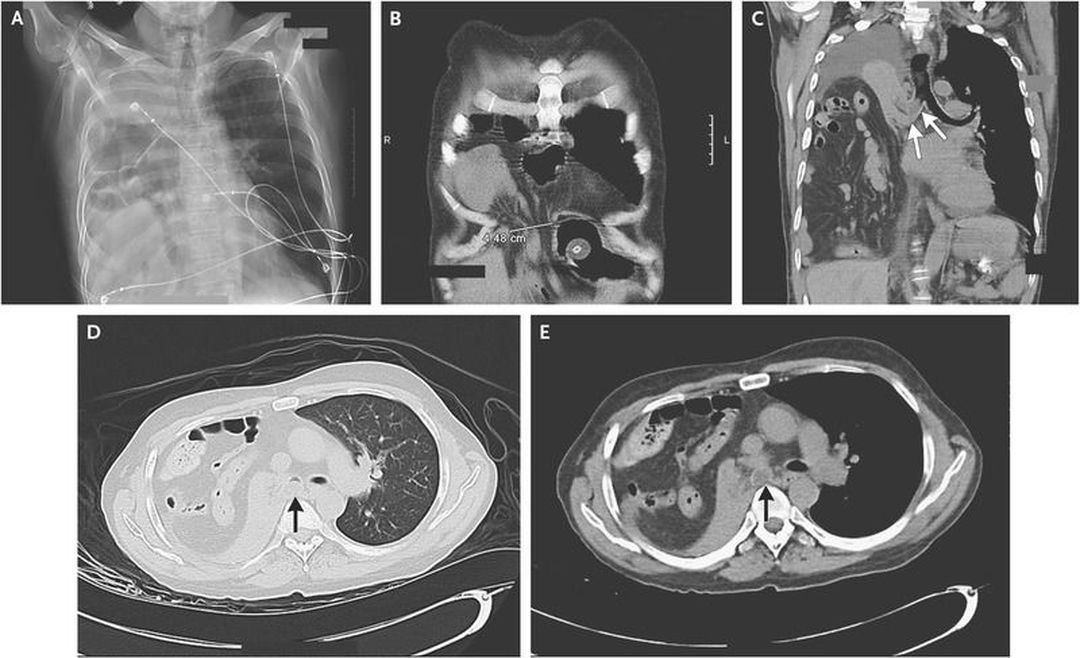

A 54-year-old man with a history of cerebral palsy and mental impairment presented with acute respiratory distress. He was afebrile and had a nonproductive cough. Physical examination revealed the use of accessory muscles of ventilation, decreased right hemithorax expansion, and an absence of breath sounds in the right hemithorax, with audible bowel sounds. The patient had mild hypoxia. A chest radiograph showed near-complete opacification of the right hemithorax, with gas-filled bowel loops on the right that extended to the level of the aortic arch (Panel A). A radiograph obtained approximately 3 months before presentation had shown a small right diaphragmatic hernia. Computed tomography of the chest performed during the current presentation confirmed the presence of a right anteromedial diaphragmatic hernia (Panel B), with a defect in the diaphragm that measured 4.5 cm in diameter. Visible within the right hemithorax was a large volume of abdominal bowel contents (Panels C, D, and E), including the majority of the right colon, the appendix, multiple loops of small bowel, mesenteric fat, and omentum. The right lung was completely collapsed, with mucous plugging of the right mainstem bronchus (arrows). There was only a mild mediastinal shift to the left, a finding that was consistent with the high degree of lung collapse accompanying the hernia and that was probably related to proximal bronchial obstruction. Because of the location of the diaphragmatic defect, the hernia was most likely a Morgagni hernia. These hernias are usually congenital in origin and can increase in size over time, as in this case. In accordance with the wishes of the patient and his family, no surgical repair was attempted.